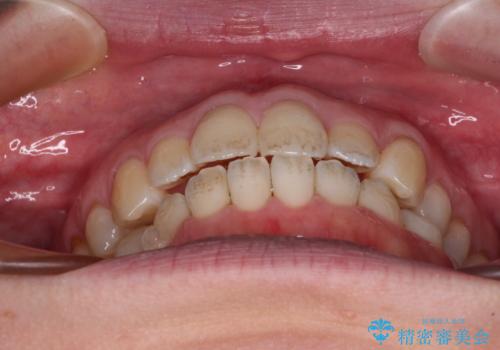

- 受け口傾向でクロスバイトの前歯を治したいとのことで来院された患者様です。

下顎骨が若干左側に変位していたため、右側にアンカースクリューを使用し、積極的に移動させながらインビザラインにて矯正治療を行うこととしました。